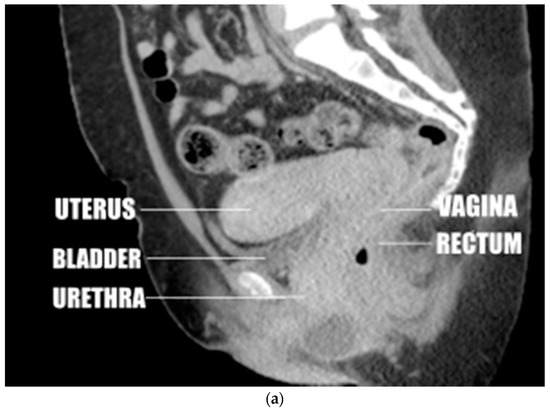

Figure 1.

(a) Anteverted uterus with the fundus near the pubic body. (b) Anteverted uterus in the most common position, close to perpendicular. (c) Anteverted uterus, above perpendicular, separated from the bladder. (d) Mildly retroverted uterus inserting at the apex of the vagina. (e) Markedly retroverted uterus inserting on the posterior wall of the vagina. Sample lines were drawn, and a sample measurement was placed on this image. The double layered line was drawn from the introitus of the vagina to the center of the surface of the cervix. The single layered line was drawn from this point parallel to the axis of the cervix.

One reader (A.A.) observed and recorded changes in the anatomic relations of the uterus to surrounding structures as the angle of version (from mild anteversion to marked retroversion) and insertion site (anterior, apical, posterior) changed, as displayed by CT and MRI. This primarily involved changes in the position of the uterus relative to the urinary bladder, vagina, and rectum (Figure 1a–e).

Observations of CT and MRI images showed that in 236 of 261 cases of anteriorly inserted anteversion, the uterine fundus was superior to and contiguous with the urinary bladder, which is supported by the urethra and the pubic body. The cervix was superior to and contiguous with the vaginal walls and the rectosigmoid colon, which is supported by the pelvic floor (Figure 1a,b).

In the remaining 25 cases of anteriorly inserted anteversion the uterine fundus was superior to and separated from the bladder, but the cervix remained immediately superior to the vaginal walls and rectosigmoid colon (Figure 1c). One uterus considered apically anteverted by measurement had the same anatomic relations.

The remaining 12 apically inserted anteverted uteri were positioned vertically, posterosuperior to the urinary bladder at a shallow angle and anterior to the rectosigmoid. The cervix was surrounded by the vaginal walls and the vaginal lumen was below the cervix. In all 44 cases of apical retroversion, the cervix was positioned vertically, posterior to the bladder and anterosuperior to the rectosigmoid at a shallow angle. The cervix was surrounded by the vaginal walls (Figure 1d). In four of these cases, the uterine fundus was contiguous with the presacral soft tissues or lower lumbar spine. In five of these cases, the uterine fundus was superior to and contiguous with the bladder when the uterus was enlarged and anteflexed.

All five posteriorly inserted retroverted uteri were superior to and contiguous with the rectosigmoid colon, which was supported by the pelvic floor and coccyx (Figure 1e).

In this study, we found that the uterus can be located along an arc extending from the pubic bone and urinary bladder to the coccyx and rectum (Figure 1a–e). Of the retroverted uteri, 89.8% were located along an arc of less than 40 degrees past the plane of the vagina before rotation was limited by the rectosigmoid colon, the lower lumbar spine, or the sacrum (Figure 1d), and 10.2% of retroverted uteri rotated further and inserted in the posterior wall of the vagina (Figure 1e). Hence, our study demonstrates that most retroversion is mild with resultant insertion of the cervix into the vaginal apex. This results in alignment of the axis of the cervix with the axis of the vagina.

We found that most anteverted uteri (95.3%) (Figure 1a–c) inserted in the anterior wall of the vagina centered on a peak of 60 to 100 degrees. A much smaller proportion of anteverted uteri (4.7%) than retroverted uteri inserted at the vaginal apex. Hence, a much smaller proportion of anteverted uteri would be subject to the postulated mechanisms leading to uterine prolapse.

Observations of images from this study appear to show that most anteriorly inserted anteverted uteri receive support from the urinary bladder, the bodies of the pubic bones, the anterior and posterior walls of the vagina, the rectosigmoid colon, and the pelvic floor (Figure 1a). The only structures below apically inserted uteri are the vaginal lumen and the urinary bladder or rectosigmoid colon at shallow oblique angles (Figure 1c). This suggests that there is less support from surrounding organs for apically inserted uteri, providing an additional possible explanation for the greater incidence of uterine prolapse in uterine retroversion.